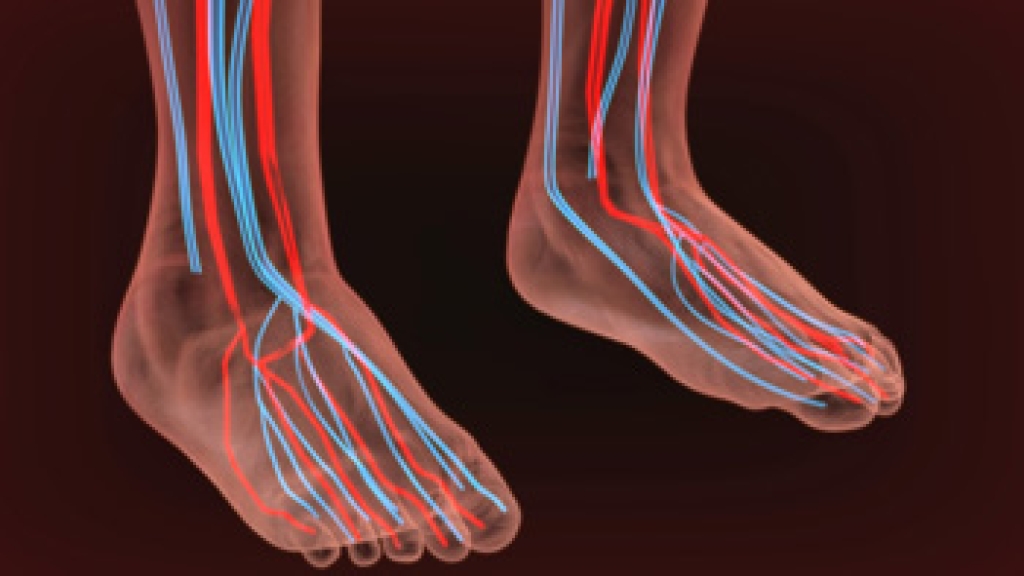

Poor foot circulation is a serious issue that can lead to various health complications if left untreated. Common warning signs include persistent coldness in the feet, even in warm environments. Numbness or tingling sensations, often described as pins and needles, can indicate circulation problems. Discoloration, such as a bluish or pale hue, may also be a sign of reduced blood flow. Swelling in the feet and ankles is another common symptom. Additionally, slow-healing sores or wounds on the feet can indicate poor circulation, as the necessary nutrients and oxygen are not efficiently reaching the area. Cramping or pain in the legs and feet, especially during physical activity, is another key indicator. Poor foot circulation can indicate serious health issues. If you have this condition, it is suggested that you visit a podiatrist who can determine what the reason is, and offer effective management tips.

Poor blood circulation in the feet and legs is can be caused by peripheral artery disease (PAD), which is the result of a buildup of plaque in the arteries.

Plaque buildup or atherosclerosis results from excess calcium and cholesterol in the bloodstream. This can restrict the amount of blood which can flow through the arteries. Poor blood circulation in the feet and legs are sometimes caused by inflammation in the blood vessels, known as vasculitis.